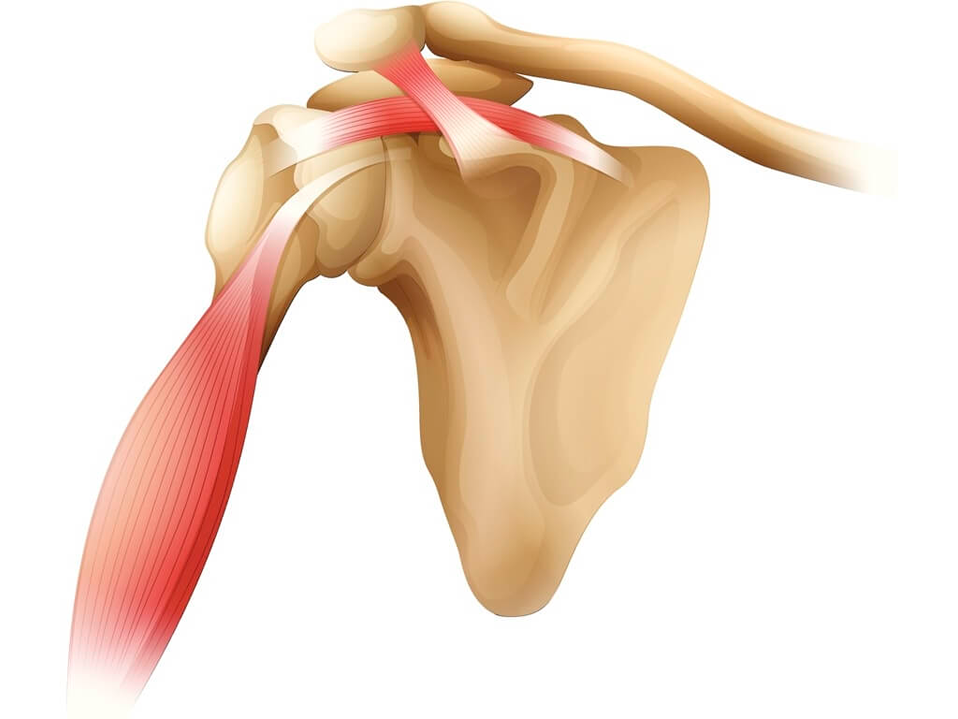

Tendinite do Bíceps

Tendinite do Bíceps

A tendinite do bíceps é a inflamação do tendão que liga o músculo bíceps ao ombro. Provoca dor na parte anterior do ombro, especialmente em movimentos de elevação e rotação. Comum em atletas e pessoas que realizam esforço repetitivo, pode ser tratada com repouso, fisioterapia e infiltrações quando necessário.